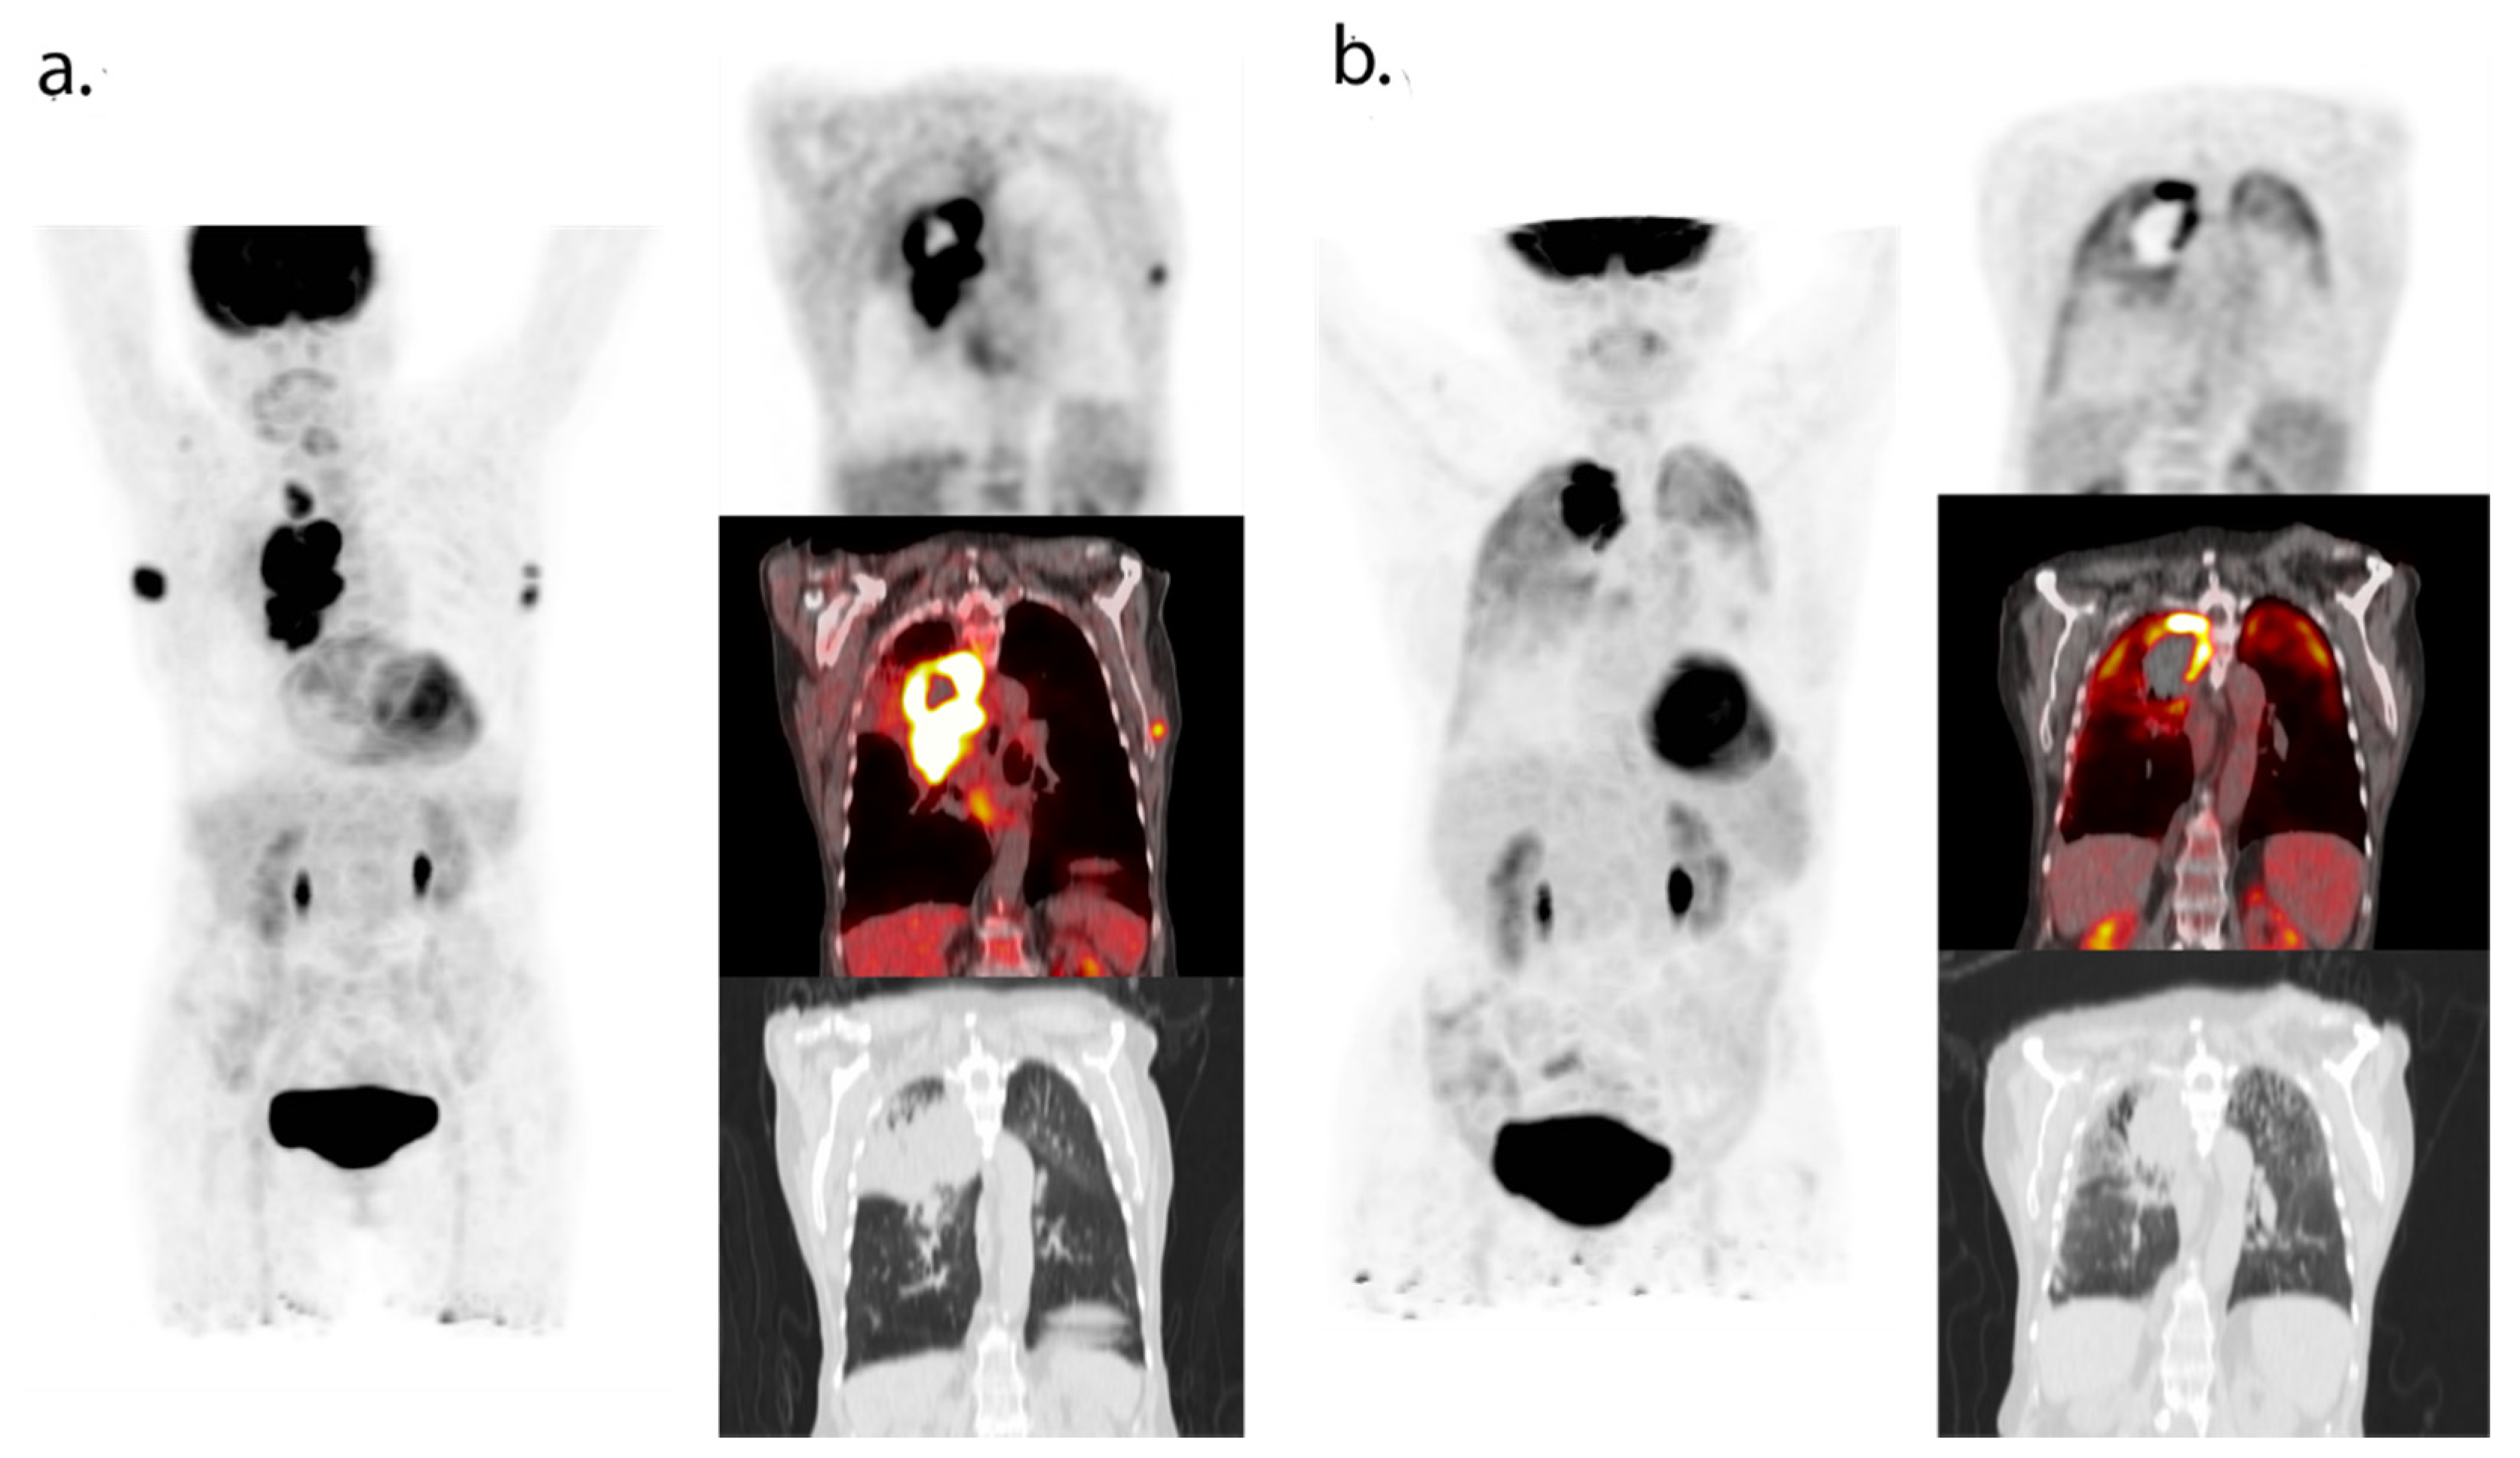

- Humbert, O.; Cadour, N.; Paquet, M.; Schiappa, R.; Poudenx, M.; Chardin, D.; Borchiellini, D.; Benisvy, D.; Ouvrier, M.J.; Zwarthoed, C.; et al. 18FDG PET/CT in the early assessment of non-small cell lung cancer response to immunotherapy: Frequency and clinical significance of atypical evolutive patterns. Eur. J. Nucl. Med. Mol. Imaging 2019, 47, 1158–1167. [Google Scholar] [CrossRef]

- Castello, A.; Rossi, S.; Toschi, L.; Lopci, E. Comparison of metabolic and morphological response criteria for early prediction of response and survival in nsclc patients treated with anti-PD-1/PD-L1. Front. Oncol. 2020, 10, 1090. [Google Scholar] [CrossRef] [PubMed]

- Tan, A.C.; Emmett, L.; Lo, S.; Liu, V.; Kapoor, R.; Carlino, M.S.; Guminski, A.D.; Long, G.V.; Menzies, A.M. FDG-PET response and outcome from anti-PD-1 therapy in metastatic melanoma. Ann. Oncol. 2018, 29, 2115–2120. [Google Scholar] [CrossRef]

- Kong, B.Y.; Menzies, A.M.; Saunders, C.A.B.; Liniker, E.; Ramanujam, S.; Guminski, A.; Kefford, R.; Long, G.V.; Carlino, M.S. Residual FDG-PET metabolic activity in metastatic melanoma patients with prolonged response to anti-PD-1 therapy. Pigment. Cell Melanoma Res. 2016, 29, 572–577. [Google Scholar] [CrossRef]